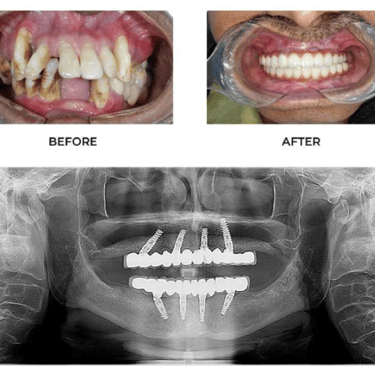

✅ Step 1: Consultation & Evaluation

Digital X-rays and oral examination.

✅ Step 2: Implant Placement

Titanium implant is placed into the jawbone.

✅ Step 3: Healing (Osseointegration)

Implant fuses with bone over few months.

✅ Step 4: Crown Placement

Custom-made tooth crown is fixed.

At Dr. Wadkar’s Dental Clinic, we specialize in replacing missing teeth with solutions that look, feel, and function exactly like natural teeth. Using the latest Digital Implant Workflow, we ensure every procedure is minimally invasive and highly predictable.

2. Full Mouth Rehabilitation

For patients with significant tooth loss, we offer comprehensive full-arch restorations. Utilizing techniques learned from masters, we stabilize your entire smile with a few strategically placed implants.

● The Benefit: Eat what you want, speak clearly, and look years younger with a stable, permanent smile.